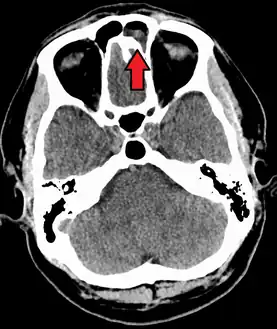

The proximity of the brain to the sinuses makes the most dangerous complication of sinusitis, particularly involving the frontal and sphenoid sinuses, infection of the brain by the invasion of anaerobic bacteria through the bones or blood vessels. Abscesses, meningitis, and other life-threatening conditions may result. In extreme cases, the patient may experience mild personality changes, headache, altered consciousness, visual problems, seizures, coma, and possibly death.[16]

Sinus infection can spread through anastomosing veins or by direct extension to close structures. Orbital complications were categorized by Chandler et al. into five stages according to their severity (see table).[26] Contiguous spread to the orbit may result in periorbital cellulitis, subperiosteal abscess, orbital cellulitis, and abscess. Orbital cellulitis can complicate acute ethmoiditis if anterior and posterior ethmoidal veins thrombophlebitis enables the spread of the infection to the lateral or orbital side of the ethmoid labyrinth. Sinusitis may extend to the central nervous system, where it may cause cavernous sinus thrombosis, retrograde meningitis, and epidural, subdural, and brain abscesses.[27] Orbital symptoms frequently precede intracranial spread of the infection . Other complications include sinobronchitis, maxillary osteomyelitis, and frontal bone osteomyelitis.[28][29][30][31] Osteomyelitis of the frontal bone often originates from a spreading thrombophlebitis. A periostitis of the frontal sinus causes an osteitis and a periostitis of the outer membrane, which produces a tender, puffy swelling of the forehead.

The diagnosis of these complications can be assisted by noting local tenderness and dull pain, and can be confirmed by CT and nuclear isotope scanning. The most common microbial causes are anaerobic bacteria and S. aureus. Treatment includes performing surgical drainage and administration of antimicrobial therapy. Surgical debridement is rarely required after an extended course of parenteral antimicrobial therapy.[32] Chronic sinus infections may lead to mouth breathing, which can result in mouth dryness and an increased risk of gingivitis. Decongestants may also cause mouth dryness.[33]

Infection of the eye socket is a rare complication of ethmoid sinusitis, which may result in the loss of sight and is accompanied by fever and severe illness. Another possible complication is the infection of the bones (osteomyelitis) of the forehead and other facial bones – Pott's puffy tumor.[16]